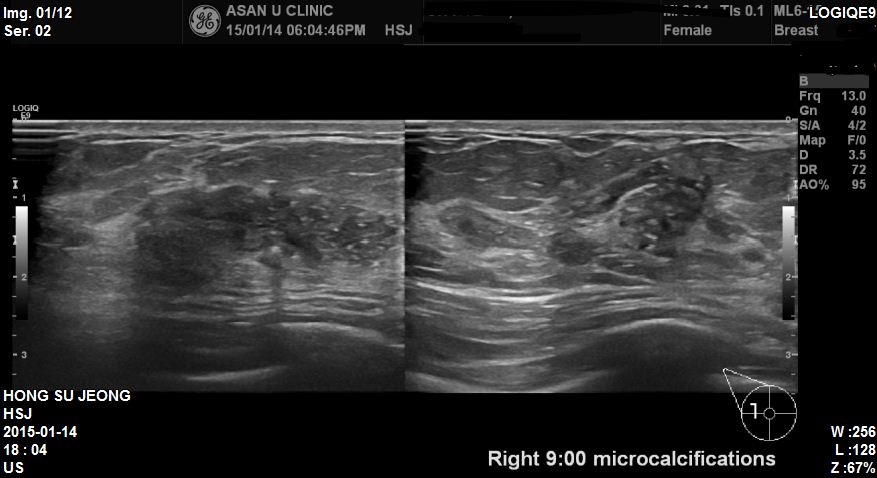

상기환자 건강검진상 이상소견으로 내원하신 58세환자분이십니다.

타원 유방초음파상 우측유방에 혹이 있었고 본원에서 부분초음파 시행후

우측 9:00방향에 미세석회화가 포함된 혹 조직검사 시행하였습니다

결과상 침윤성유방암진된되었습니다.